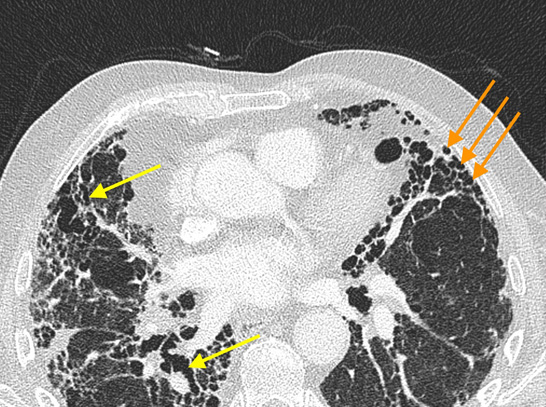

Santosham Chest Hospital offers CT Guided biopsies. Dr. Roy Santosham our Interventional Radiologist is an expert in CT guided Biopsies, Radio Frequency Ablation for inoperable tumors, Vertebral Biopsy, Vertebroplasty, Nerve root and Facet injections and Coeliac plexus block for pain relief.

A CT Guided Biopsy is a way of obtaining a small piece of tissue from an area that looks potentially abnormal. We use the CT Scanner to guide us to the right area to obtain the tissue. The CT Scanner is a machine, which uses X-rays and a Computer to produce a series of cross sectional pictures through the patient. These scans show much more detail than can be appreciated on an ordinary X-ray picture. Most people having a biopsy will have had a CT Scan already but for those who have not, the CT Scanner is a large square box with a big round hole through it’s middle, rather like a huge square donut or polo mint. The patient being scanned lies on a table, which passes through the hole in the machine the table is then positioned so that the area being scanned is in the centre of the hole.